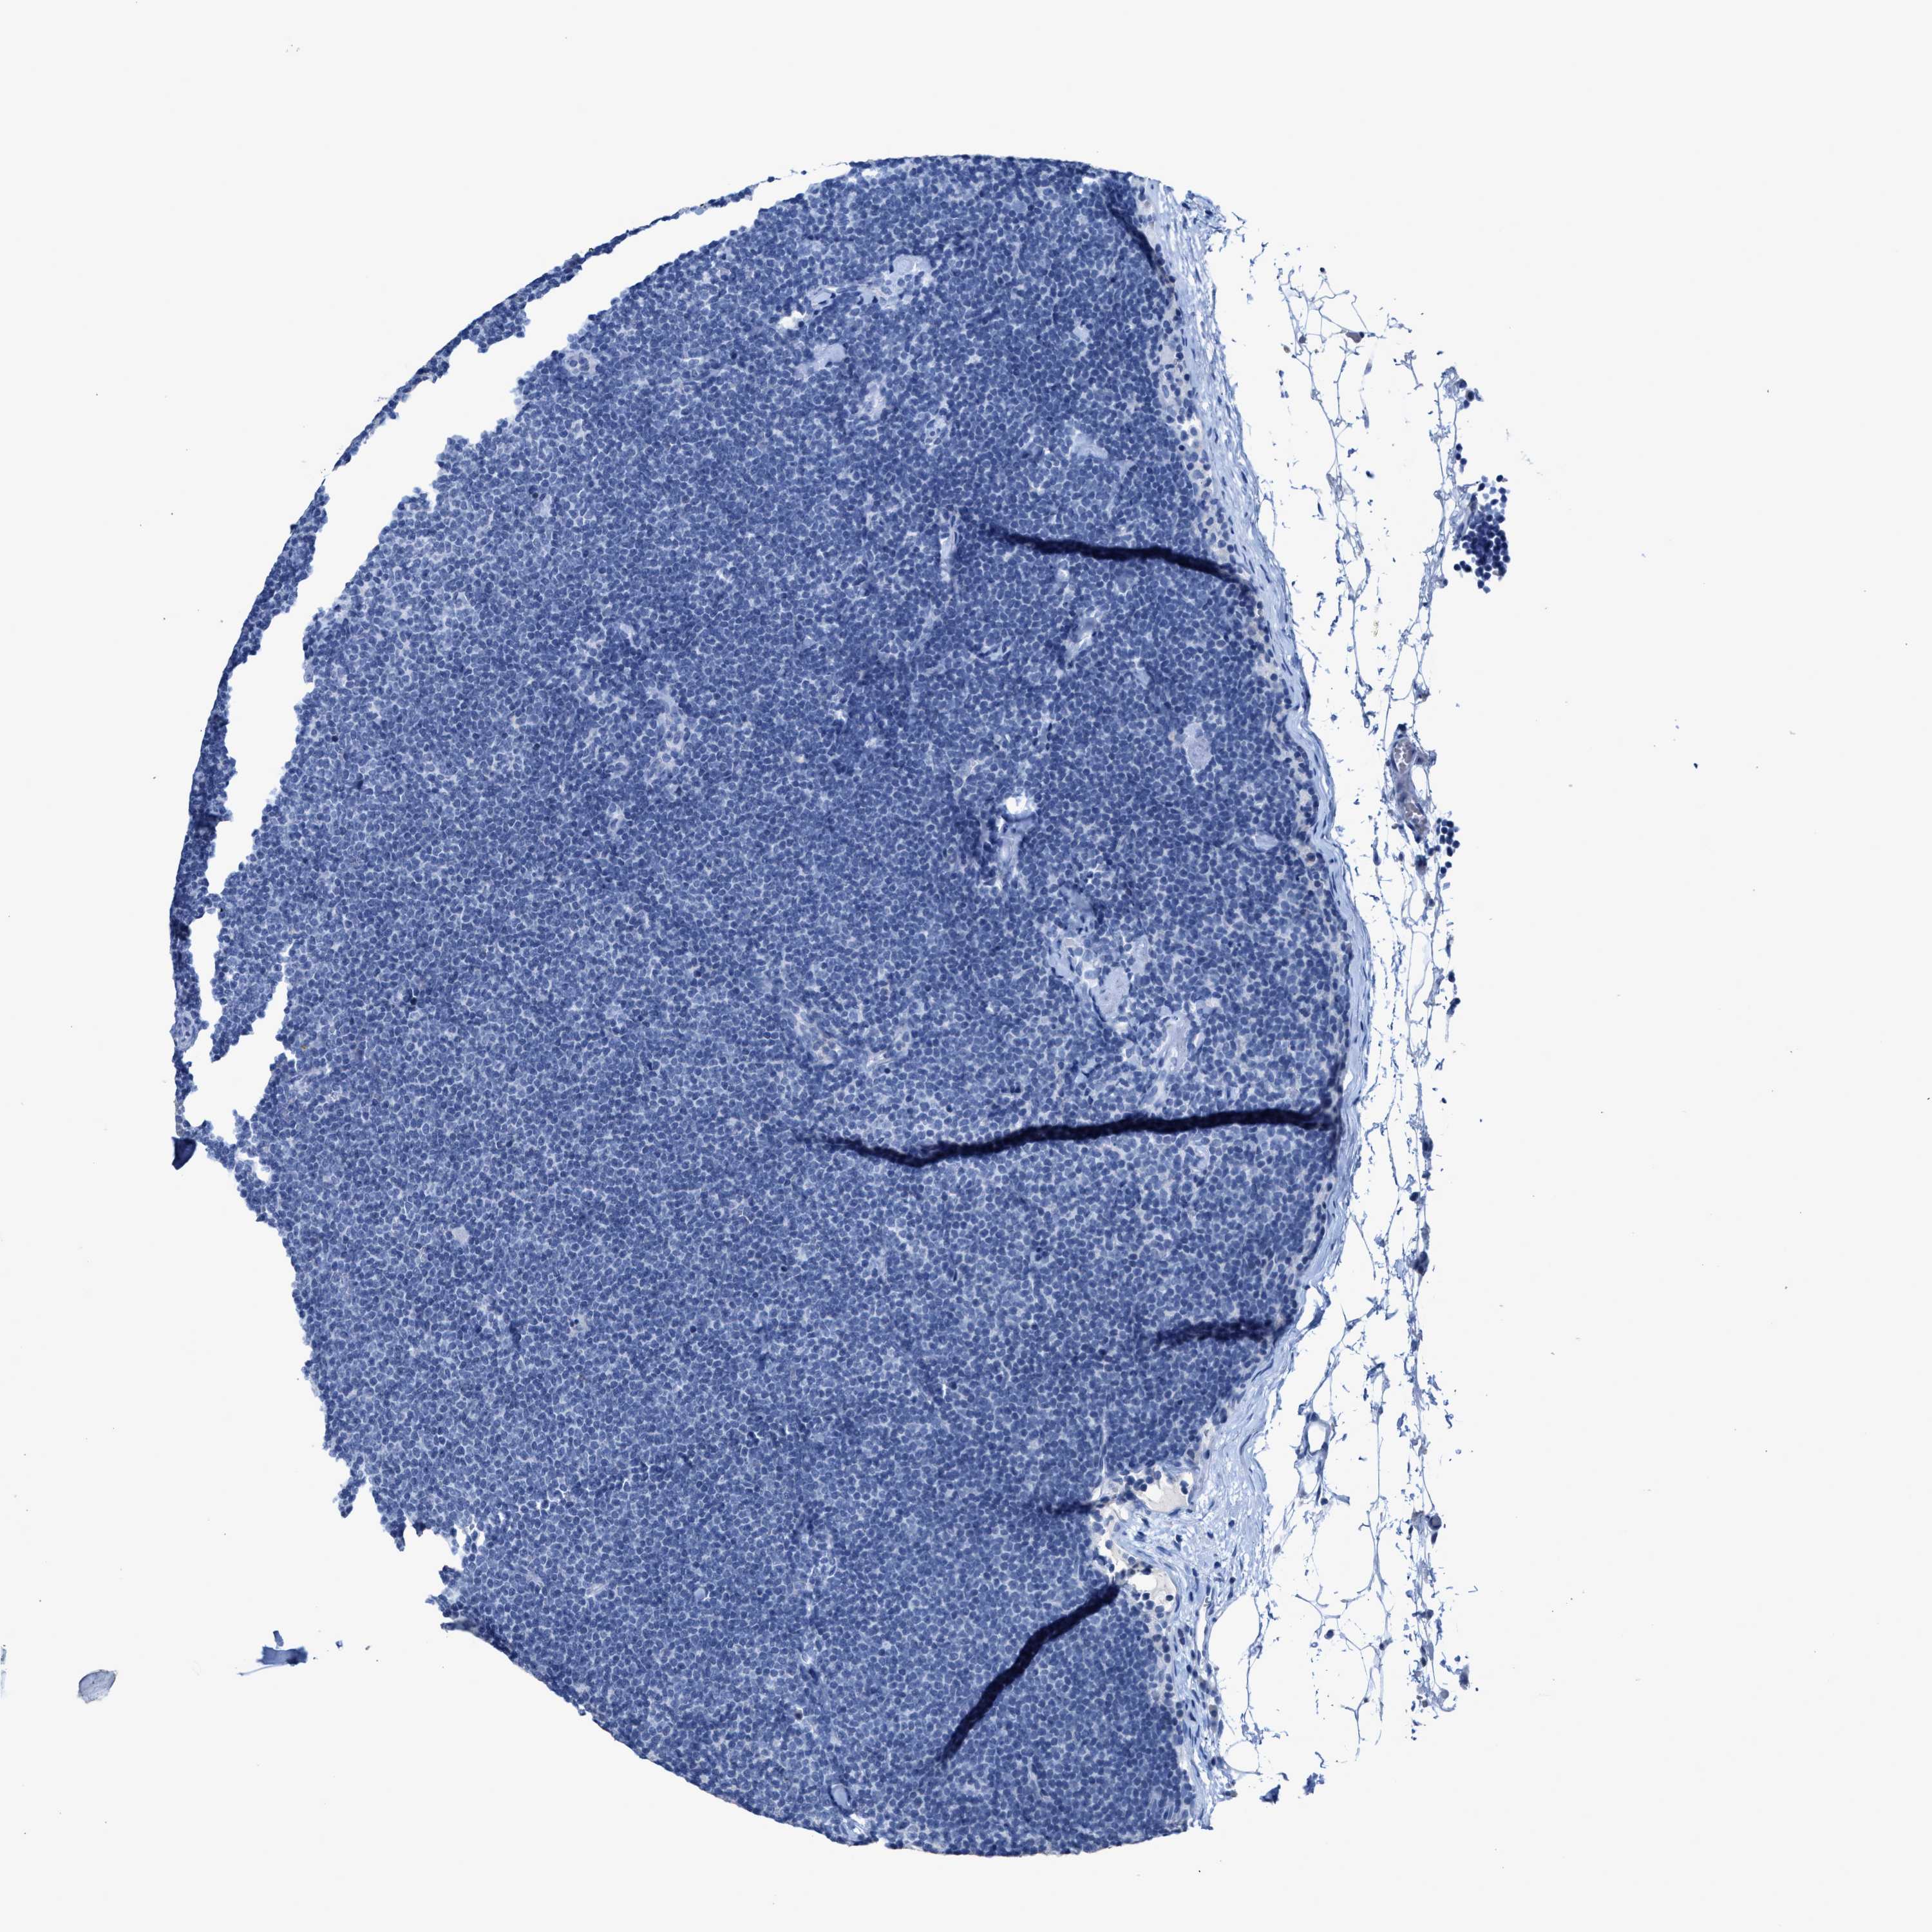

LYMPHOMA - Protein expressioni

A mouse-over function shows sample information and annotation data. Click on an image to view it in a full screen mode. Samples can be filtered based on level of antibody staining by selecting one or several of the following categories: high, medium, low and not detected. The assay and annotation is described here.

Each image is clickable and will lead to virtual microscopy that enables deeper exploration of all samples and also displays staining intensity scores, fraction scores and subcellular localization as well as patient and tissue information for each sample.

Antibody CAB000021

Hodgkin's disease, NOS

Malignant lymphoma, non-Hodgkin's type, Low grade

Malignant lymphoma, non-Hodgkin's type, High grade